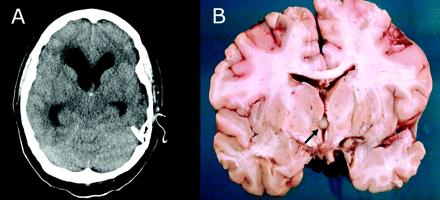

19岁以前健康的女人面对横贯大陆的飞行后突然头痛和恶心。她迅速进入昏迷。CT扫描显示摘要脑积水(图)。缓解颅内压的心室插入排水,但她的临床状况未能改善。病人在入院24小时内死亡。最值得注意的发现尸检胶体囊肿妨碍室间孔。一些类似的病例报告。1、2我们得出这样的结论:病人窝藏胶体囊容易气压性创伤与致命的结果。